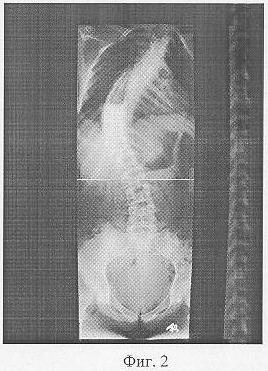

Фиг.2 – копии рентгенограмм до лечения пациентки С.с определением углов деформации;

Предоперационная подготовка включала в себя диагностирование деформации позвоночника для уточнения диагноза и дальнейшего проектирования оперативного вмешательства по типу «Закрытый остеосинтез позвоночника аппаратом наружной транспедикулярной фиксации». При диагностике были выполнены спондилограммы. Используя их измеряли углы деформации и определяли плоскость, направление, области и участки приложения дозированных усилий.